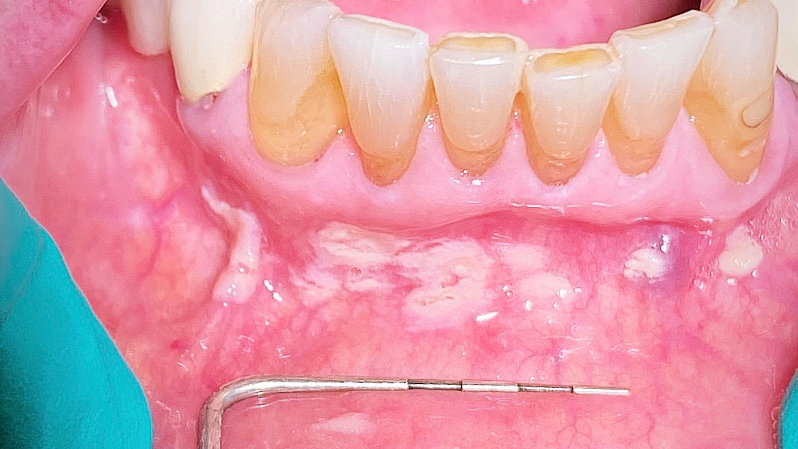

Take a look at the initial photograph. What’s the first thing that comes to your mind? Scattered, white, creamy patches in the lower anterior vestibule, each measuring approx. 3–6 mm (figure 1). Now, take a look at the second picture after the white patches were easily wiped off with gauze (figure 2). Note the red, thin membraned tissue? It was very tender to the touch.This diagnosis should be a slam dunk by now. Yup, you guessed it. Good ol’ pseudomembranous candidiasis, aka thrush.

- Acute pseudomembranous candidiasis consists of creamy, loose patches of desquamative epithelium that are easily removed.1 Red tissue tender to the touch is what is painful to the patient.

- Chronic hyperplastic candidiasis consists of white plaques or papules against an erythematous background; it’s asymptomatic and does not rub off.1 A case presented earlier was diagnosed to be this form of thrush.